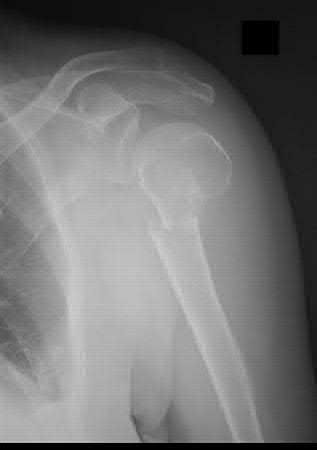

Question 7:

A 55-year-old active female undergoes a primary total hip arthroplasty. The surgeon opts for a ceramic-on-ceramic bearing surface to maximize longevity. Which of the following complications is uniquely associated with this specific bearing couple compared to metal-on-polyethylene?

Options:

- Trunnionosis

- Squeaking

- Galvanic corrosion

- Accelerated osteolysis from submicron particles

- Pseudotumor formation

Correct Answer: Squeaking

Explanation:

Squeaking is an audible complication unique to hard-on-hard bearings, specifically ceramic-on-ceramic (CoC) total hip arthroplasties. It occurs in up to 10% of CoC THAs and may be related to component malposition, edge loading, or microseparation. Trunnionosis and galvanic corrosion are associated with modular junctions (like a metal head on a metal stem). Pseudotumors are classically linked to metal-on-metal bearings.